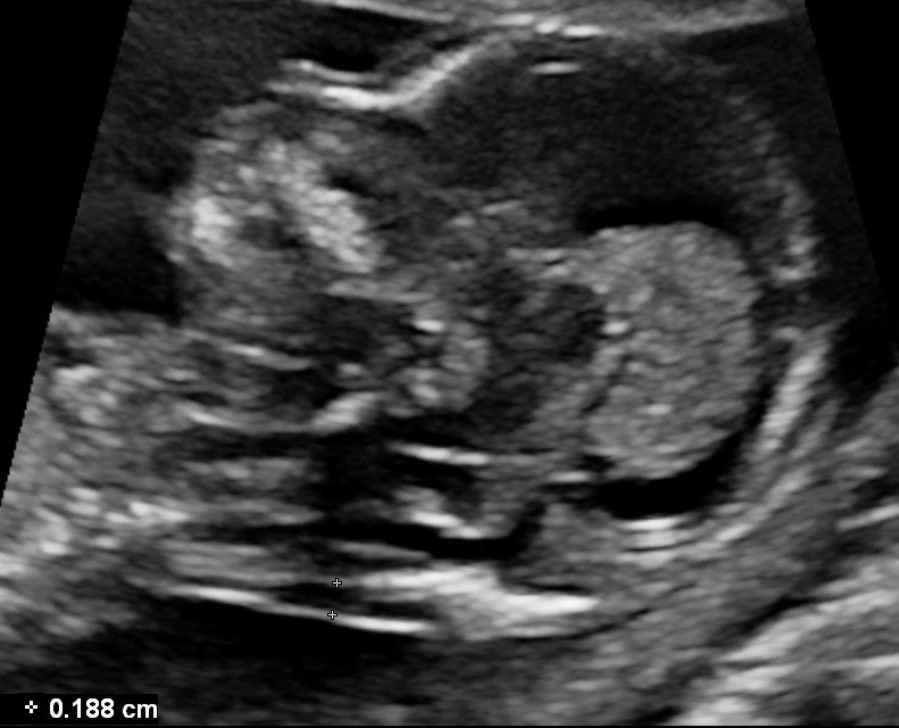

Measure the Fetal Abdomen

fetal abdomen ultrasound correct plane